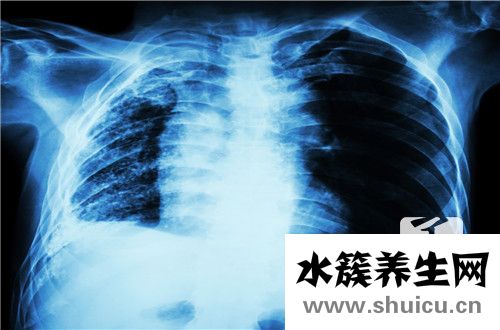

結核性腹膜炎是一種非常常見的腹部疾病,在女性中最常見。 主要癥狀通常是全身腹脹,腹痛,發燒和汗水,很容易失去能量,缺乏能量和精力。 這種疾病是由結核病引起的。 在由感染引起的腹部,治療應徹底立即,如果不能立即則很容易產生其他胃腸道疾病,例如腸穿孔。

結核性腹膜炎因病理學種類和機體反映性的不一樣而異。一般發病遲緩,早期癥狀比較輕;極少數發病急劇,以急性腹痛或乍起高燒為關鍵臨床癥狀;有時候發病隱襲,無顯著病癥,僅從和該病不相干的腹部病癥在手術治療進到腹部時,才被出現意外發覺。

1、腹痛 初期腹痛不顯著,之后可出現持續性隱疼或隱隱作痛,還可以自始至終沒有腹痛。疼痛多坐落于臍周、下腹,有時候在全腹。腹痛除因為腹膜炎自身造成外,常和伴隨的活躍性腸結核、腸系膜淋巴結結核或盆腔結核相關。當高并發不完全性腸梗阻時,有陣發劇痛。偶可主要表現為急腹癥,是由于腸系膜淋巴結結核或腹部內醫、學教育信息網收集整理別的結核病的奶酪樣壞死疾病潰破造成,也可由腸結核亞急性破孔引發。

2、全身病癥 結核病毒血癥普遍,主要是發熱與盜汗。間歇熱以低燒與中等水平熱為數最多,約1/3病人有弛張熱,極少數可出現稽留熱。高燒伴隨顯著毒血癥者,關鍵常見于奶酪型、外滲型,或常見于伴隨奶酪樣肺炎、粟粒型肺結核等比較嚴重結核病的病人。中后期有營養不良,主要表現為削瘦、貧血、水腫、舌炎、口角炎等。

3、腹部觸診 腹腔柔韌性感是腹膜后遭到輕微刺激性或有炎癥的一種主要表現,是結核性腹膜炎的普遍臨床癥狀。腹部壓痛一般輕度;極少數壓疼比較嚴重,而且有反跳痛,多見于奶酪型結核性腹膜炎。

4、肝腹水 經常出現腹脹感,可由結核病毒血癥或腹膜炎伴隨腸功能紊亂造成,不一定有肝腹水。

結核性腹膜炎的肝腹水以小量至中測為多見,小量肝腹水在臨床醫學查驗中不容易察出,因此務必用心查驗。

5、腹部腫塊 常見于黏連型或奶酪型,常坐落于臍周,也可坐落于別的位置。硬塊多由腫脹的腸系膜淋巴結節、變厚的大網膜、黏連結團的腸曲或奶酪樣壞死膿狀物堆積而成,其大小不一,表層高低不平,邊沿不齊。有時候呈包塊感。活動力小。

6、別的 腹瀉普遍,排泄物多呈糊樣,一般每天不超過3~4次。腹瀉有多種多樣醫、學教育信息網收集整理原因,除腹膜炎引發的腸功能紊亂外,可由伴隨的潰瘍型腸結核或奶酪樣壞死變病造成的腸道內瘺等造成。

有時候腹瀉與便秘更替出現,肝大并許多 見,可因營養不良引發脂肪肝或肝結核造成。

病發癥以腸梗阻為普遍,多產生于黏連型。腸瘺一般常見于奶酪型,通常另外有腹部囊腫產生。